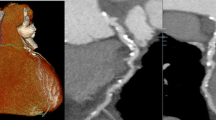

CCTA in patient with ACP: 3D VR a and curved MPR b well show non-calcified plaques in proximal and mid LAD with PR (b–d), suggesting for vulnerable plaques (ACP acute chest pain, LAD left anterior descending artery, MPR multiplanar reconstruction, 3D VR three-dimensional volume rendering, PR positive remodeling)